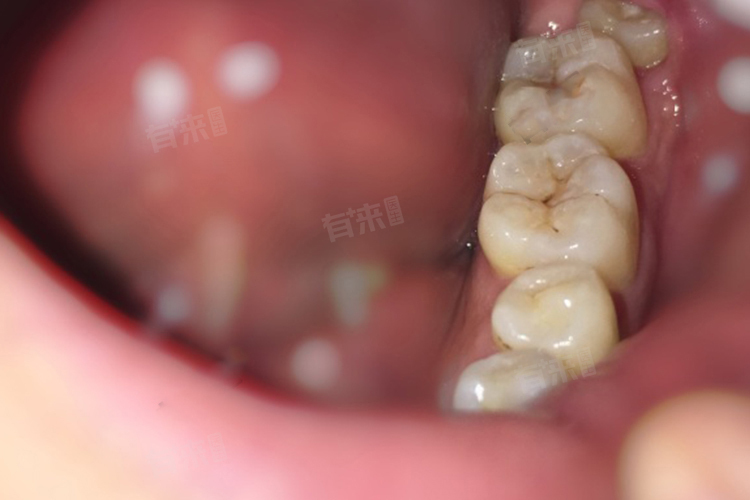

- 这种空间不足常常会引发一系列问题,智齿可能会出现阻生的情况,即不能正常萌出到口腔内,而是部分或全部被牙龈或周围的骨头覆盖。阻生智齿容易引起周围牙龈的炎症、肿胀和疼痛,也就是我们常说的智齿冠周炎。智齿还可能会挤压相邻的牙齿,导致牙齿排列不齐,甚至引起相邻牙齿的龋齿、牙周炎等问题。